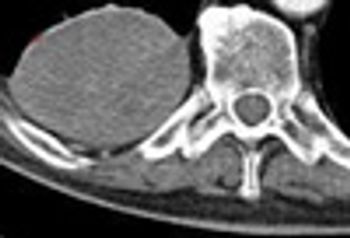

A 71-year-old man was admitted to the MICU for weaning from mechanical ventilation. The history revealed a global decline over the previous 3 to 4 weeks predominated by cognitive impairment, mood swings, somnolence, and limb weakness. No respiratory symptoms were noted.